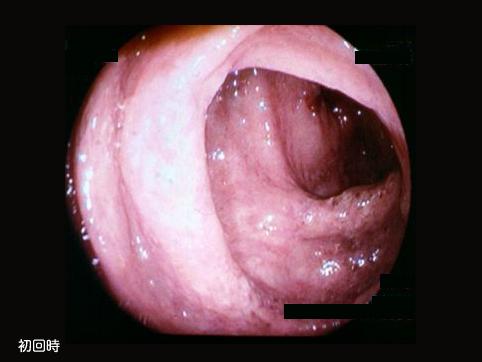

A case of Escherichia coli O 157 : H7-associated colitis.

Hokkaido Pref., Hokkaido P.W.F.A.C Sapporo-Kosei general Hospital (Dr.Imamura)

Inflammatory or ulcerative disease / lesions/Escherichia coli associated colitis

Large intestine(Colon)/Ascending colon

Endoscopy